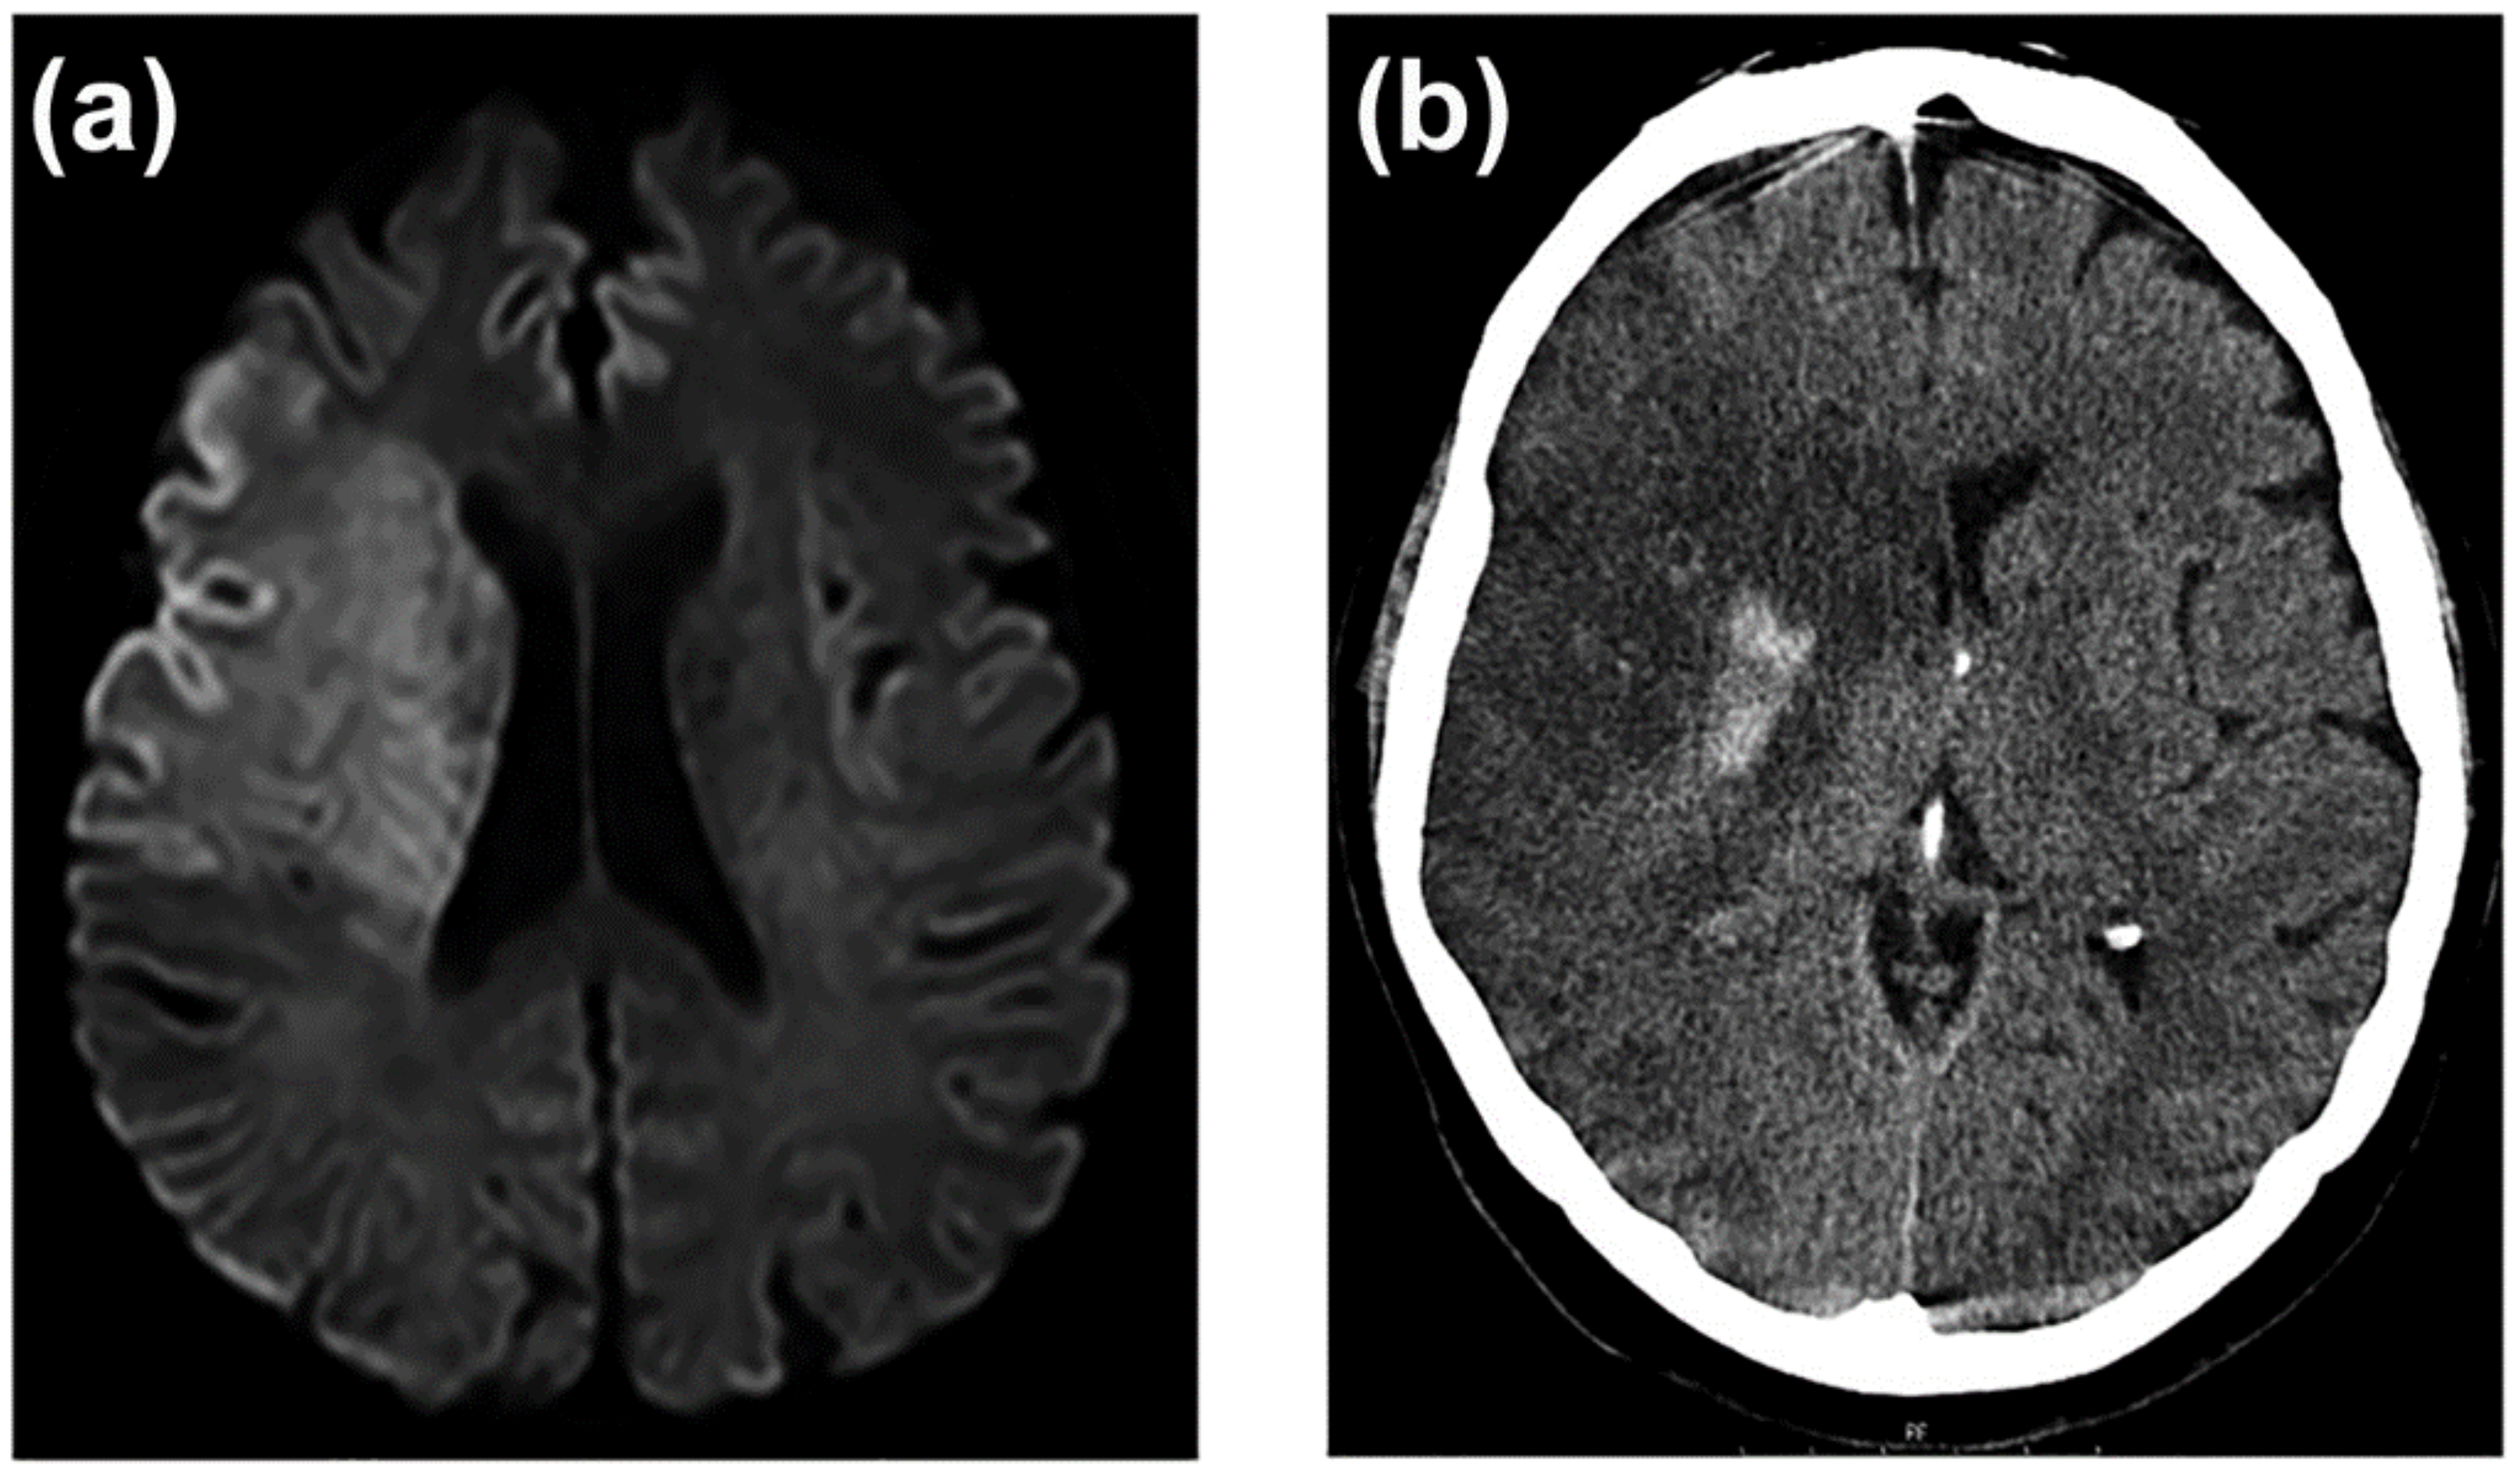

3.7. Neuroimaging of BBB Dysfunction

- Heiss, W.-D. Malignant MCA Infarction: Pathophysiology and Imaging for Early Diagnosis and Management Decisions. Cerebrovasc. Dis. 2016, 41, 1–7. [Google Scholar] [CrossRef] [PubMed]

- Wu, M.-N.; Fang, P.-T.; Hung, C.-H.; Hsu, C.-Y.; Chou, P.-S.; Yang, Y.-H. The Association between White Matter Changes and Development of Malignant Middle Cerebral Artery Infarction. Medicine 2021, 100, e25751. [Google Scholar] [CrossRef] [PubMed]

- Hoehn-Berlage, M.; Norris, D.G.; Kohno, K.; Mies, G.; Leibfritz, D.; Hossmann, K.A. Evolution of Regional Changes in Apparent Diffusion Coefficient during Focal Ischemia of Rat Brain: The Relationship of Quantitative Diffusion NMR Imaging to Reduction in Cerebral Blood Flow and Metabolic Disturbances. J. Cereb. Blood Flow Metab. 1995, 15, 1002–1011. [Google Scholar] [CrossRef] [PubMed]

- Von Kummer, R.; Meyding-Lamadé, U.; Forsting, M.; Rosin, L.; Rieke, K.; Hacke, W.; Sartor, K. Sensitivity and Prognostic Value of Early CT in Occlusion of the Middle Cerebral Artery Trunk. AJNR. Am. J. Neuroradiol. 1994, 15, 9–15; discussion 16–18. [Google Scholar]